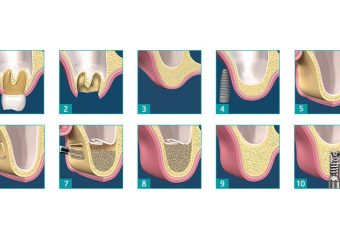

- ایمپلنت دندان اصفهان